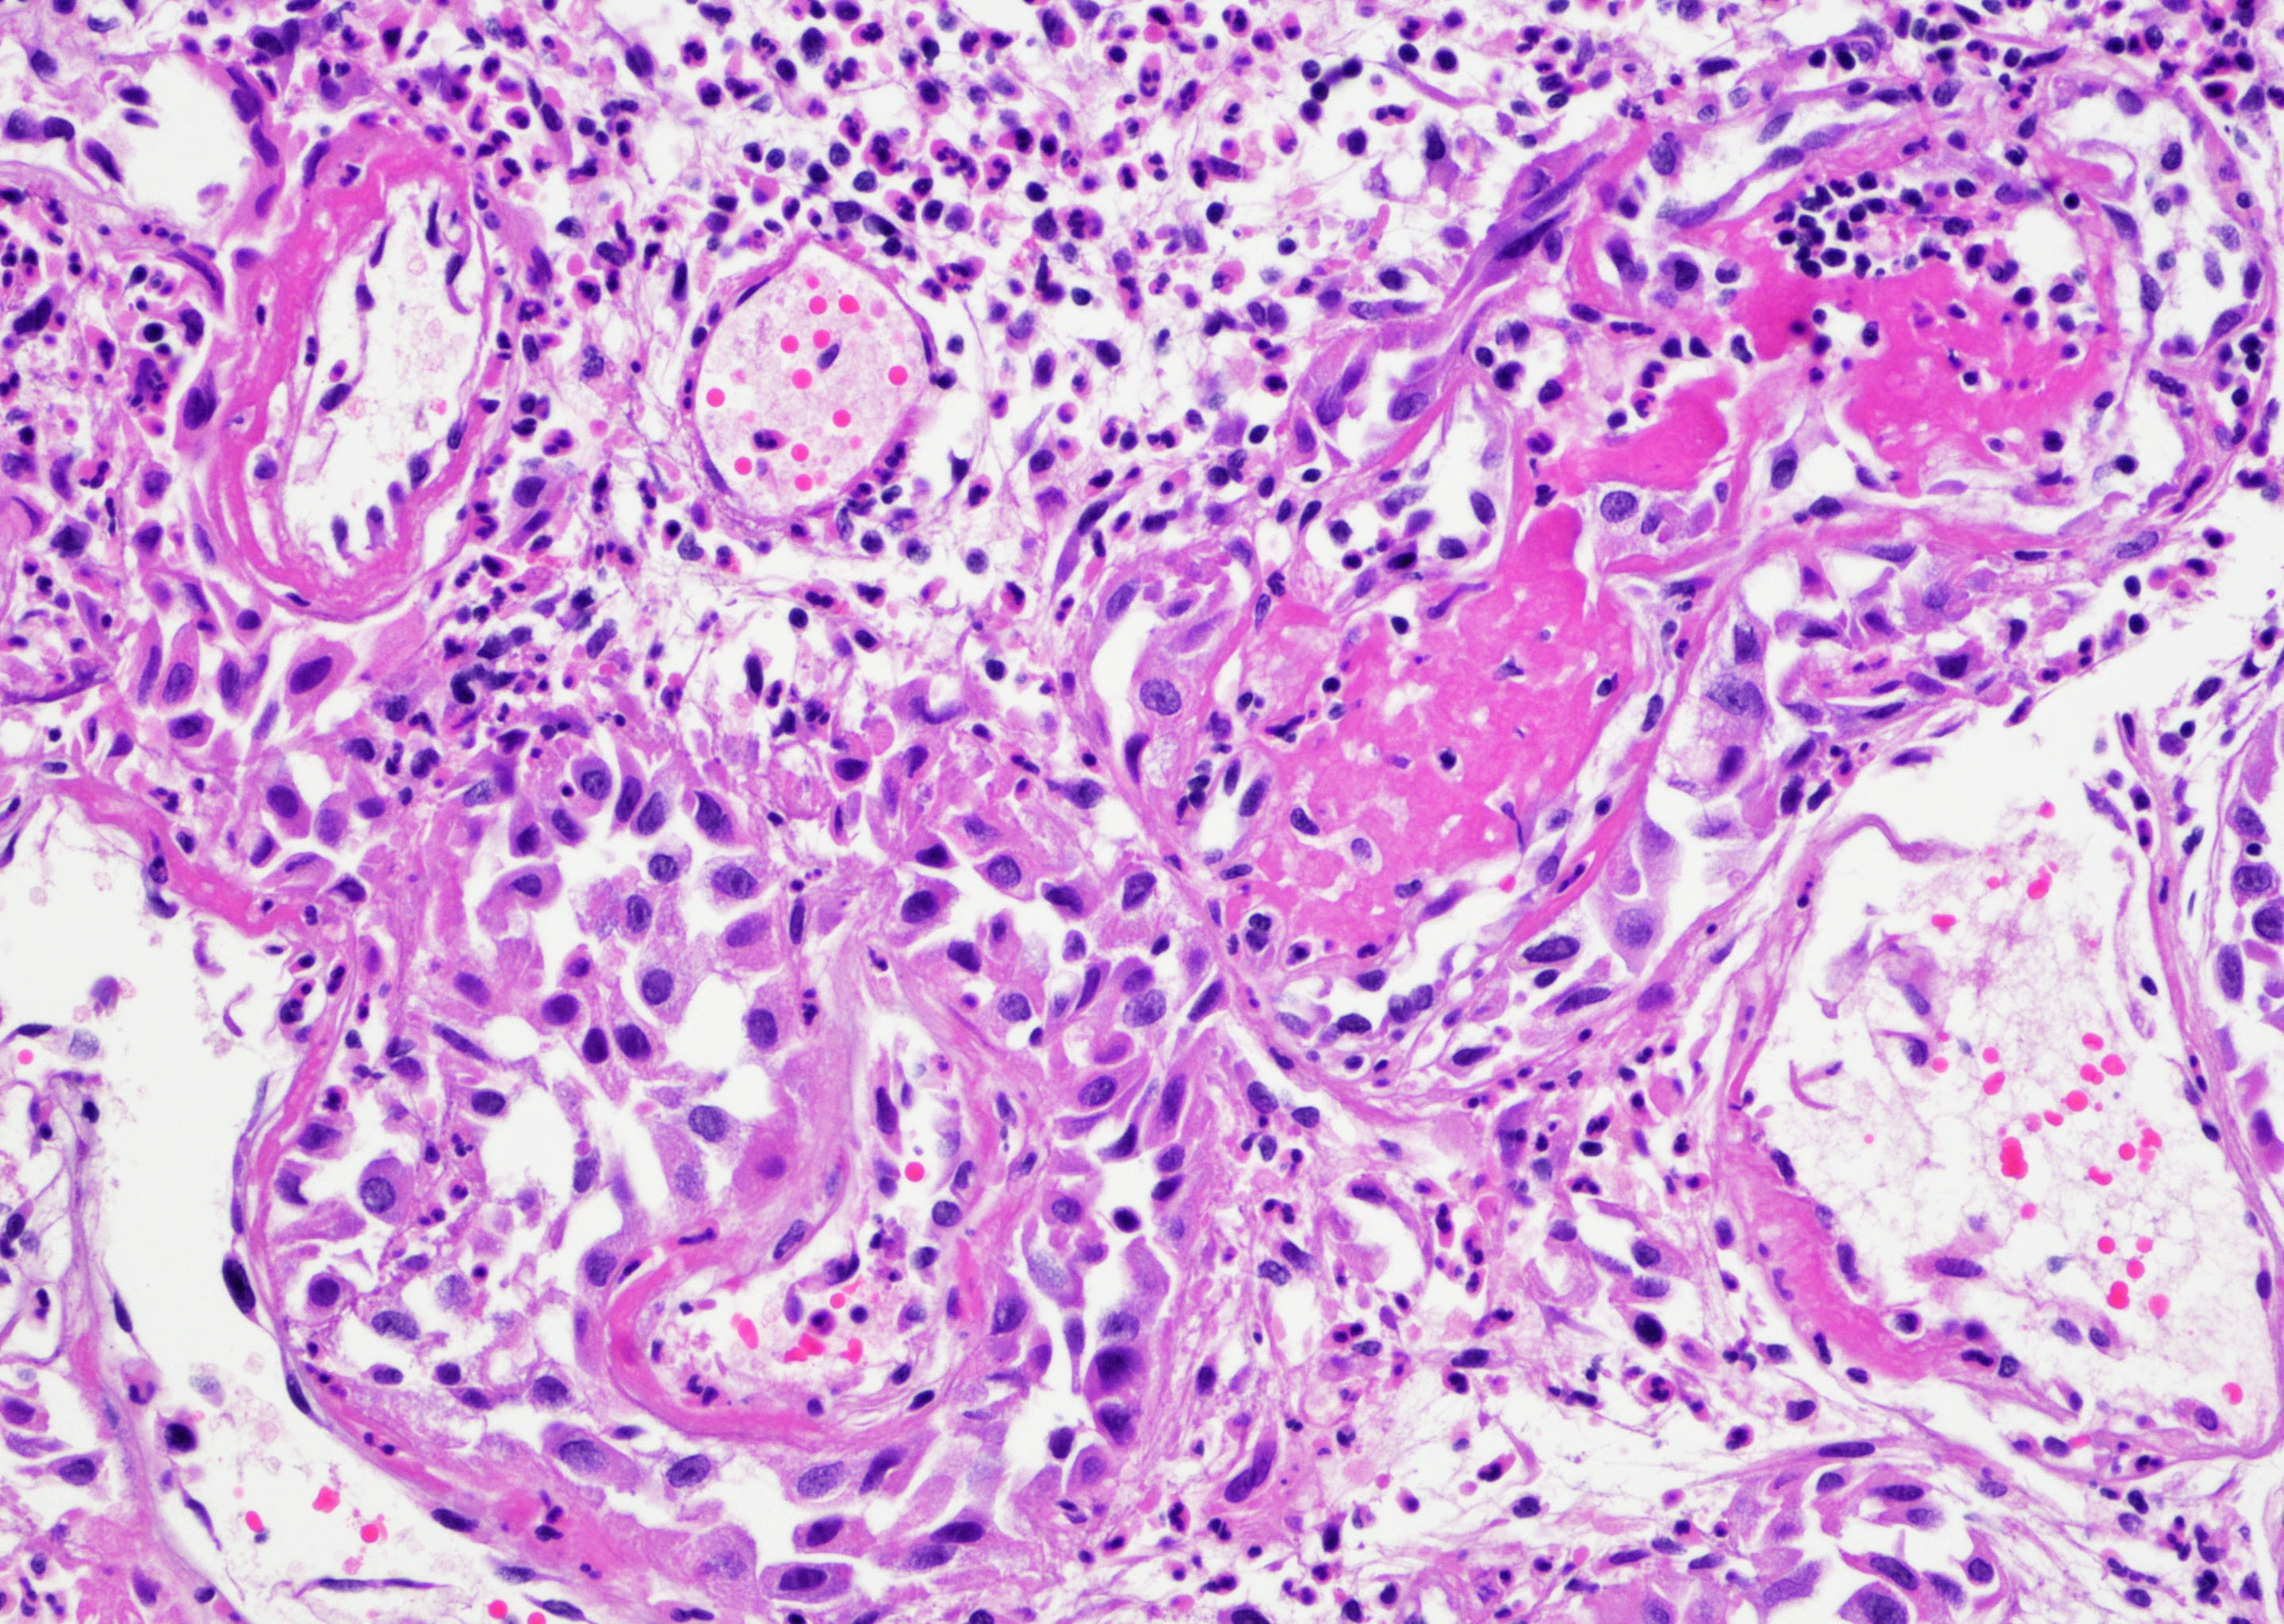

- Vessels with fibrin thrombi, fibrinoid vascular necrosis, vascular congestion, thickened walls, endothelial proliferation and telangiectasia

- Acute and chronic inflammation

- Reactive multinucleated stromal fibroblasts with smudgy nuclei

- Fibrosis and edema

- Hemorrhage and hemosiderin

- Pseudocarcinomatous urothelial hyperplasia: variable sized urothelial cords and nests with rounded or irregular edges present in the lamina propria and enclose dilated blood vessels with fibrin deposition (Am J Surg Pathol 2008;32:92)

- Acute phase: edematous, congested and telangiectatic vessels, acute and chronic inflammatory infiltrate, atypical stromal cells with multinucleated forms

- Chronic phase: atrophic urothelium, atrophic smooth muscle layer, collagen deposition (fibrosis) (Am J Surg Pathol 2004;28:909)

Microscopic (histologic) images

Contributed by Y. Albert Yeh, M.D., Ph.D. and Jennifer Lee, M.D.

- Comment: There is a history of radiation therapy per the medical record. The transurethral resection of the bladder lesion shows fragments of urothelial mucosa with total and partial denudation of urothelium. The urothelial lining cells show reactive changes. There is marked edema, hemorrhage and mixed inflammatory infiltrate composed predominantly of neutrophils and lymphocytes in the lamina propria. Reactive multinucleated stromal fibroblasts are seen. Telangiectatic vessels with fibrinoid necrosis and intravascular fibrin deposition are seen. Anastomosing cords and nests of urothelial cells encircling the vessels with fibrin deposition is evident. Urothelial cells with hyperchromatic nuclei, increased nuclear to cytoplasmic ratio and prominent nucleoli are seen. These features are consistent with radiation cystitis with pseudocarcinomatous urothelial hyperplasia. Muscularis propria is not identified in this specimen.

A 68 year old man presented with hematuria and dysuria. He has a medical history of prostate cancer that was treated with radiation therapy. Cystoscopy revealed hemorrhage in the right bladder wall. A transurethral resection of the lesion was performed. A photomicrograph is shown above. What is the diagnosis?

- Radiation cystitis with pseudocarcinomatous hyperplasia

C. Radiation cystitis with pseudocarcinomatous hyperplasia. Answers A, B and D are incorrect because anastomosing cords and nests of urothelial cells encircling ectatic vessels with intravascular and stromal fibrin deposition in a background of mixed inflammation are not present in these entities.